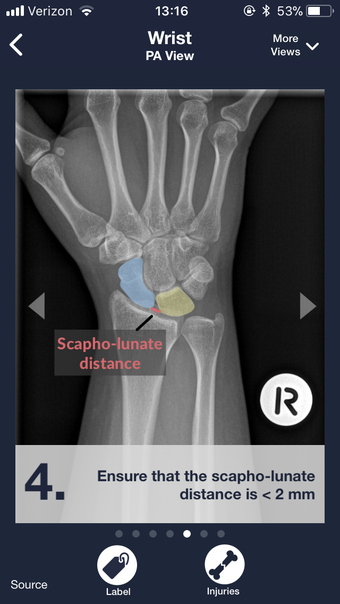

To help you get familiar with the different radiology findings, we have created a stepwise approach to each condition. This approach is based on the findings that are most important for the diagnosis, and the evidence-based management of each condition.

The app includes hundreds of different radiology findings, along with their corresponding diagnoses and clinical pearls and insights.